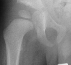

RESULT: ROM: R. knee 0-110 degrees, L. knee 0-120 degrees.; he started

ambulating 18 months with a well reduced femoral head

.